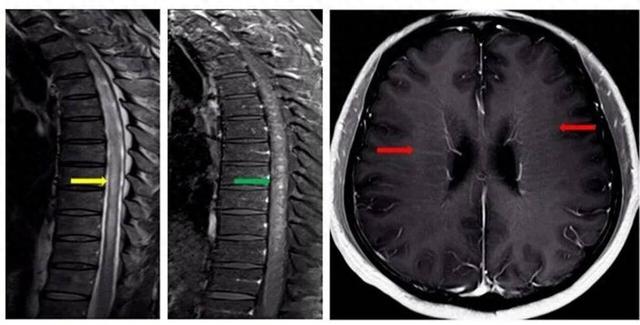

万分焦虑之下,陈老师慕名找到了南京市第一医院神经内科主任医师、医学博士时建铨,在仔细梳理了陈老师病情后,时建铨认为对称性下肢无力、上肢感觉异常及排尿功能障碍这三个症状看似互不相关,但串联在一起则指向了同一个方向,可能存在脊髓方面问题。时建铨给陈老师安排了脊髓+头颅增强核磁共振检查,结果提示:脊髓长节段异常信号(图1中黄色箭头)伴斑片状强化(图1中绿色箭头),且脑室周围存在线样放射状强化(图1中红色箭头)。

专家指出,该病典型影像学特征为头颅核磁共振检查显示脑室周围线样放射状强化;脊髓核磁共振检查显示颈胸段脊髓长节段异常信号伴斑片状强化。脑脊液抗GFAP抗体阳性是确诊的核心证据。